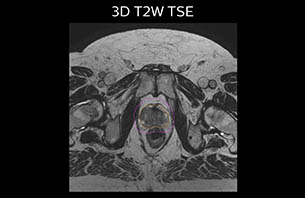

A 77-year-old male with prostate cancer cT3aN0M0, Gleason 8 and PSA 52 μg/L referred to androgen deprivation and radiation therapy with a prescribed dose of 50 Gy to the pelvic lymph node regions and 76 Gy to the prostate.

MR-only simulation workflow The 3D T1W FFE mDIXON sequence provides in-phase, water and fat images in one acquisition. Target and organs-at-risk are delineated on the 3D T2W TSE images. Prostate GTV is shown in orange, PTV in purple. The 3D bFFE sequence is used by the planner to mark the position of the fiducial markers (gold anchors) and contours are transferred to the digitally reconstructed radiographs (DRRs).